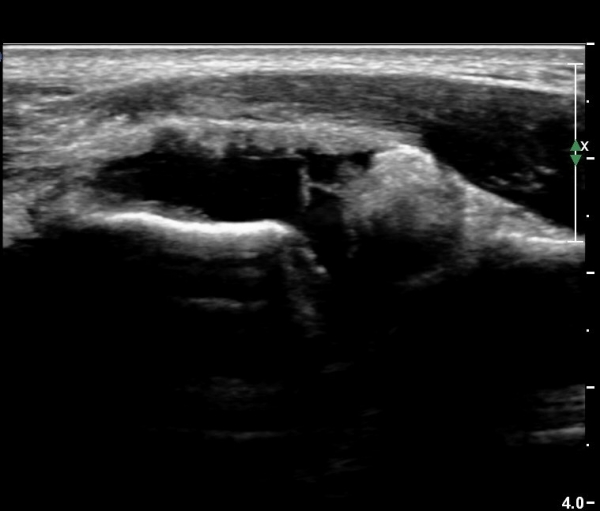

ÃÊÀ½ÆÄ °Ë»ç

ÆÈ²ÞÄ¡ ¾ÕÂÊ ¼ÒµÎ Á¾´Ü¸é°Ë»ç¿Í Ⱦ´Ü